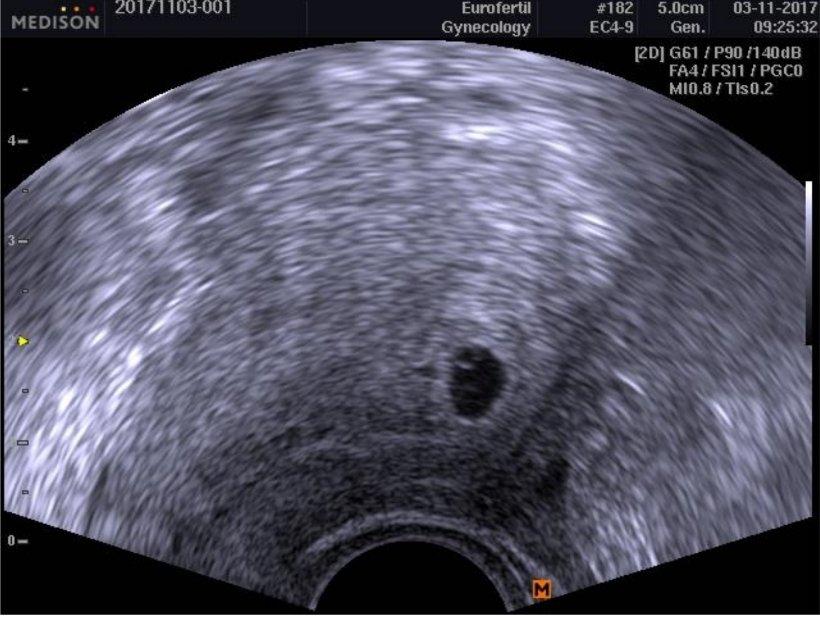

@volfici Taaaak vše je na svém místě. Jde vidět i gestační váček. Na srdeční odezvy je prý brzy a uvidíme se zase za týden (to už by snad to srdíčko mohlo jít slyšet). Jinak mám zákaz číst diskuze, protože jsem se ho ptala jak je možné, že mi vůbec nic není (ani prsa, ani nevolnost, prostě vůbec nic). Tak se smál, že to přijde a že už nesmím řešit s žádnou těhulí kde kdo čím trpí :D Jinak tady je pidi fazolka